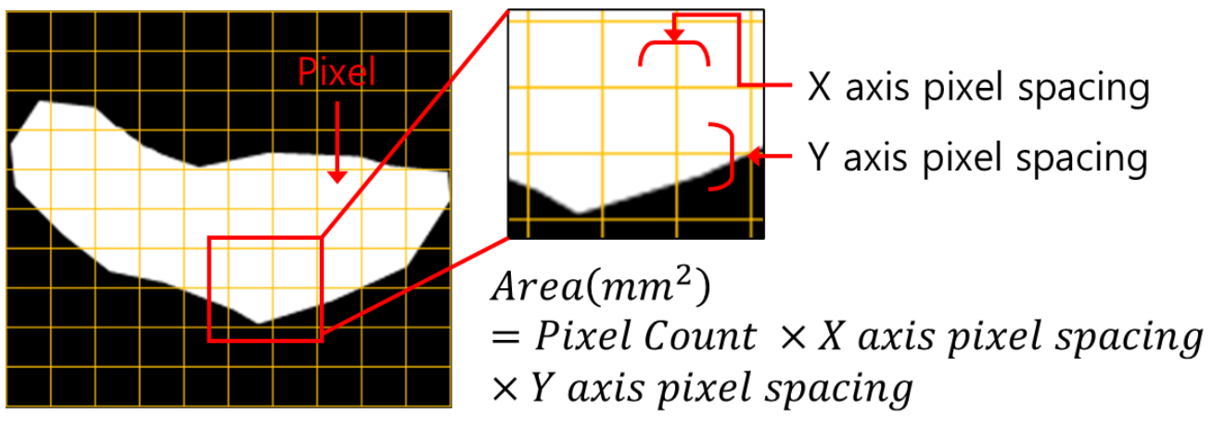

3. T2 Axial에서의 척수 영역 분할 및 면적 측정 모델

- 모델 학습

- 바이오 의료 영상 분야에서 분할을 목적으로 만들어진 모델을 사용하여 학습을 진행.

- Erode 및 Dilate, Median Blur를 이용해 이미지 후처리. Noise 및 Hole 제거

[T2 MRI에서 척수 영역 분할 모델 개요]

- 척추 면적 측정

- Dicom Header의 Pixel Spacing 정보를 통해 AI 결과에 대한 면적(mm2) 측정

[척추 영역 면적 측정]